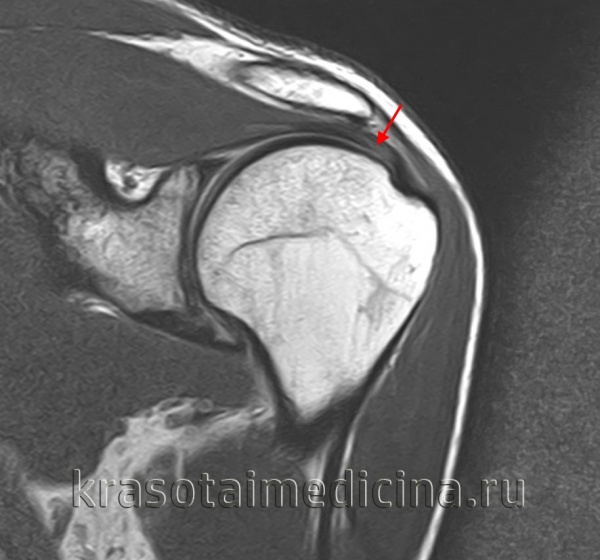

Диагноз повреждения ахиллова сухожилия выставляется на основании клинических данных, при необходимости может использоваться МРТ. В первые двое суток при незначительном расхождении концов сухожилия возможно консервативное лечение. На конечность накладывают гипс в положении максимального подошвенного сгибания сроком на 6 недель. При застарелых повреждениях и неудаче консервативной терапии показана операция.

Для уточнения диагноза используется сравнительная рентгенография коленных суставов (надколенник с больной стороны смещен кверху), МРТ коленного сустава и УЗИ сустава. Лечение оперативное, осуществляется в стационарных условиях. Колено разгибают, концы связки сближают и соединяют при помощи матрацных швов. При отрыве костной пластинки накладывают трансоссальные швы. Иммобилизацию продолжают 2-3 недели. После операции назначают антибиотики и анальгетики, в последующем – ЛФК, ультразвук, диадинамические токи, парафин и массаж.

Диагноз обычно устанавливают на основании типичных клинических признаков, в отдельных случаях пациентов направляют на УЗИ и МРТ. Лечение хирургическое, осуществляется в плановом порядке в условиях стационара. Сухожилие сшивают матрацными швами, рану ушивают послойно и дренируют. Руку фиксируют при помощи клиновидной подушки на 2-3 недели. Затем назначают тепловые процедуры, массаж и ЛФК.

Диагноз уточняют при помощи УЗИ или МРТ. При неполных разрывах накладывают гипс на 3-6 недель, затем назначают ЛФК. При полных разрывах сухожилие сшивают в условиях стационара. При свежих повреждениях применяют матрацные швы, при застарелых разрывах производят удлинение сухожилия с использованием лоскута из четырехглавой мышцы. Послеоперационную иммобилизацию осуществляют в течение 6 недель, в реабилитационном периоде назначают озокерит, парафин, ультразвук, массаж и ЛФК.